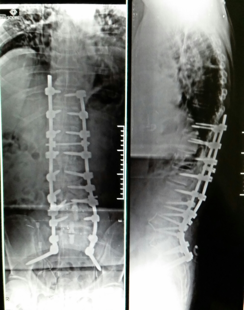

Nestes casos, a correção cirúrgica em pacientes clinicamente favoráveis deve ser levada em consideração dois aspectos, tanto a correção da deformidade quanto a descompressão dos nervos a fim de promover a recuperação funcional do paciente.

Casos como este, devemos fazer a cirurgia em várias etapas, com descompressão posterior e liberação articular e ligamentar (“posterior release”) e depois correção da curvatura por via anterior abdominal (ALIF). Só assim conseguimos corrigir corretamente este tipo de deformidade.

Neste exemplo o paciente apresenta importante deformidade no plano sagital com escoliose degenerativa compensada no plano coronal. A correção feita objetivou a correção das duas deformidades (plano sagital e coronal) e descompressão posterior.

Veja que a cirurgia corrigiu a escolise e principalmente restaurou a linha de prumo sagital, que proporciona uma melhora da qualidade de vida e correção do equilíbrio global da coluna.